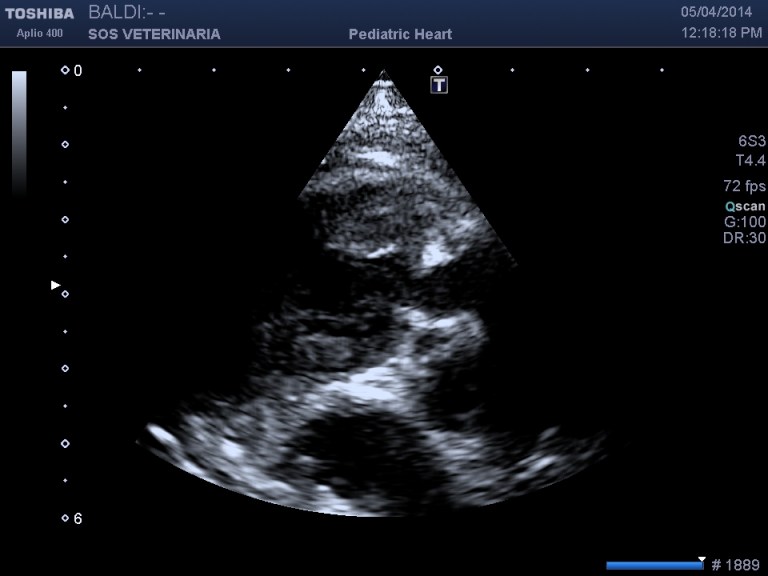

parasternale craniale sx asse corto ottimizzata per il tratto di efflusso destro

Sul piano ecocardiografico non e’ facile emettere diagnosi, raramente con la tradizionale ecocardiografia toracica si riesce a vedere la coronaria anomala ,contrariamente all’esame transesofageo a cui bisogna ricorrere nei casi fortemente dubbi prima di eseguire la valvuloplastica.

Questo Buldog di nome Ettore e’ stato presentato alla visita con soffio sistolico all’eta’ di tre mesi ed episodi di broncopolmonite ricorrente scarsamente responsiva alla terapia ,dall’esame ecocardiografico a mio avviso rientra in una diagnosi di anomalia della coronaria destra ed e’ stato deciso solo per il trattamento con beta bloccanti .

Nella visione delle immagini e dei filmati richiamo l’attenzione ad alcuni criteri di semplice reperibilita’ che portano la diagnosi verso questa anomalia :

- imponente il grado di ipertrofia concentrica ventricolare destra con gradienti molto elevati superiori ai 100 mmHg (anche 160mmHg),il cuore ha subito fin da subito un necessario rimodellamento alla condizione

- L’anello stenotico e’ sempre piccolo

- difficilmente si visualizzano i lembi valvolari in quanto il restringimento dell’anulus generato dal passaggio della coronaria impedisce la loro apertura ,in transtoracica si possono visualizzare dritti come canne al vento

- nelle scansioni in cui si intravedono i lembi valvolari nessun effetto doming appare visualizzabile( come nella stenosi polmonare classica di tipo A)

- invece di lembi valvolari si visualizza un cordoncino simil fibroso il diametro della stenosi e’ sempre piccolo

Non esistono trattamenti , i beta bloccanti possono aiutare a ridurre i rischi di morte improvvisa